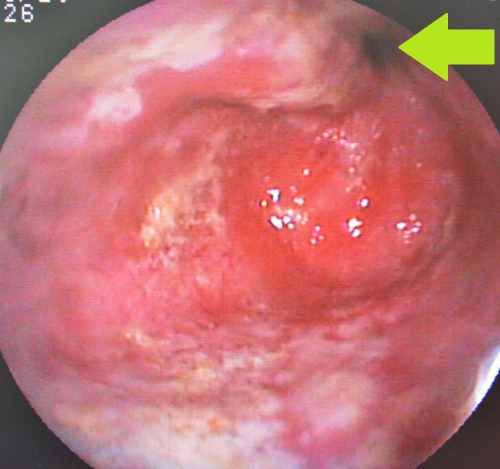

さらに食道は異物による内側からの圧迫に弱く、またその修復能力も高くありません。下の写真は異物を摘出した後のものですが、黄色矢印の先が凹んで周囲の粘膜から出血しています、その中央部は異物に圧迫されて潰瘍を作っています。また、緑矢印の先の赤黒い部分は粘膜面にうっ血が生じて、食道粘膜に広くダメージを起こしているのが分かります。